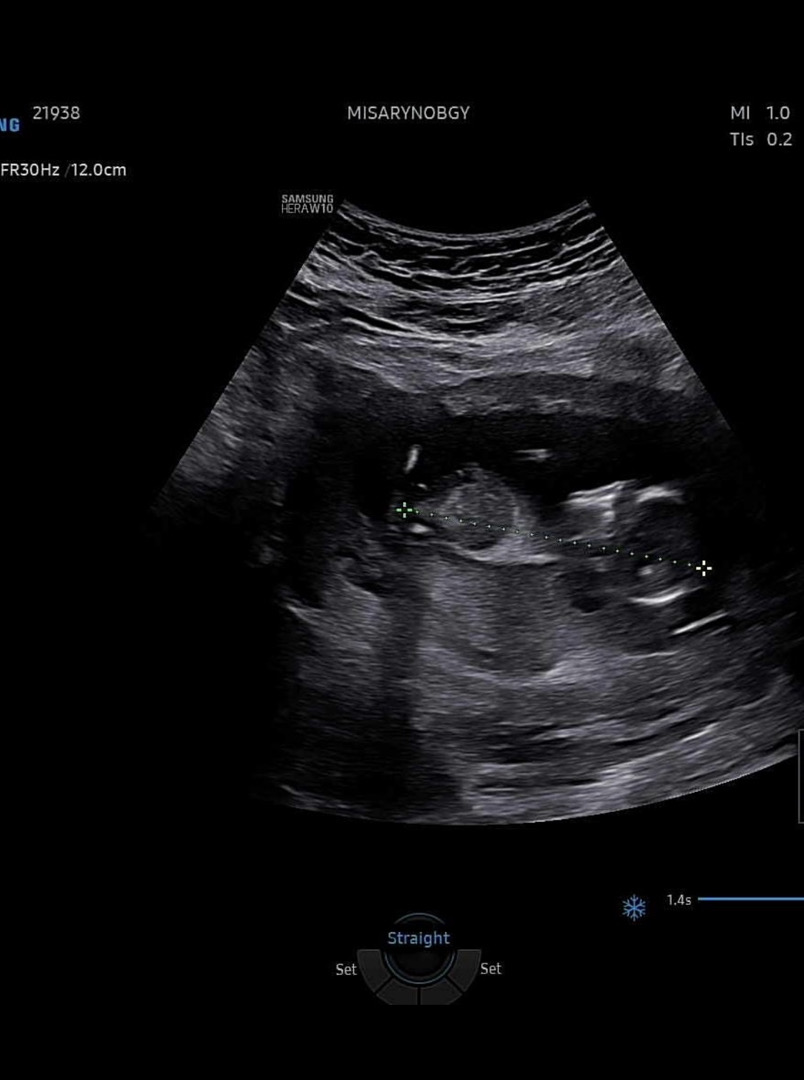

각도법 봐주세요~~

딸일까요? 아들일까요?? 저는 각도법 찾아봐도 뭔지 모르겠어요ㅜㅜ